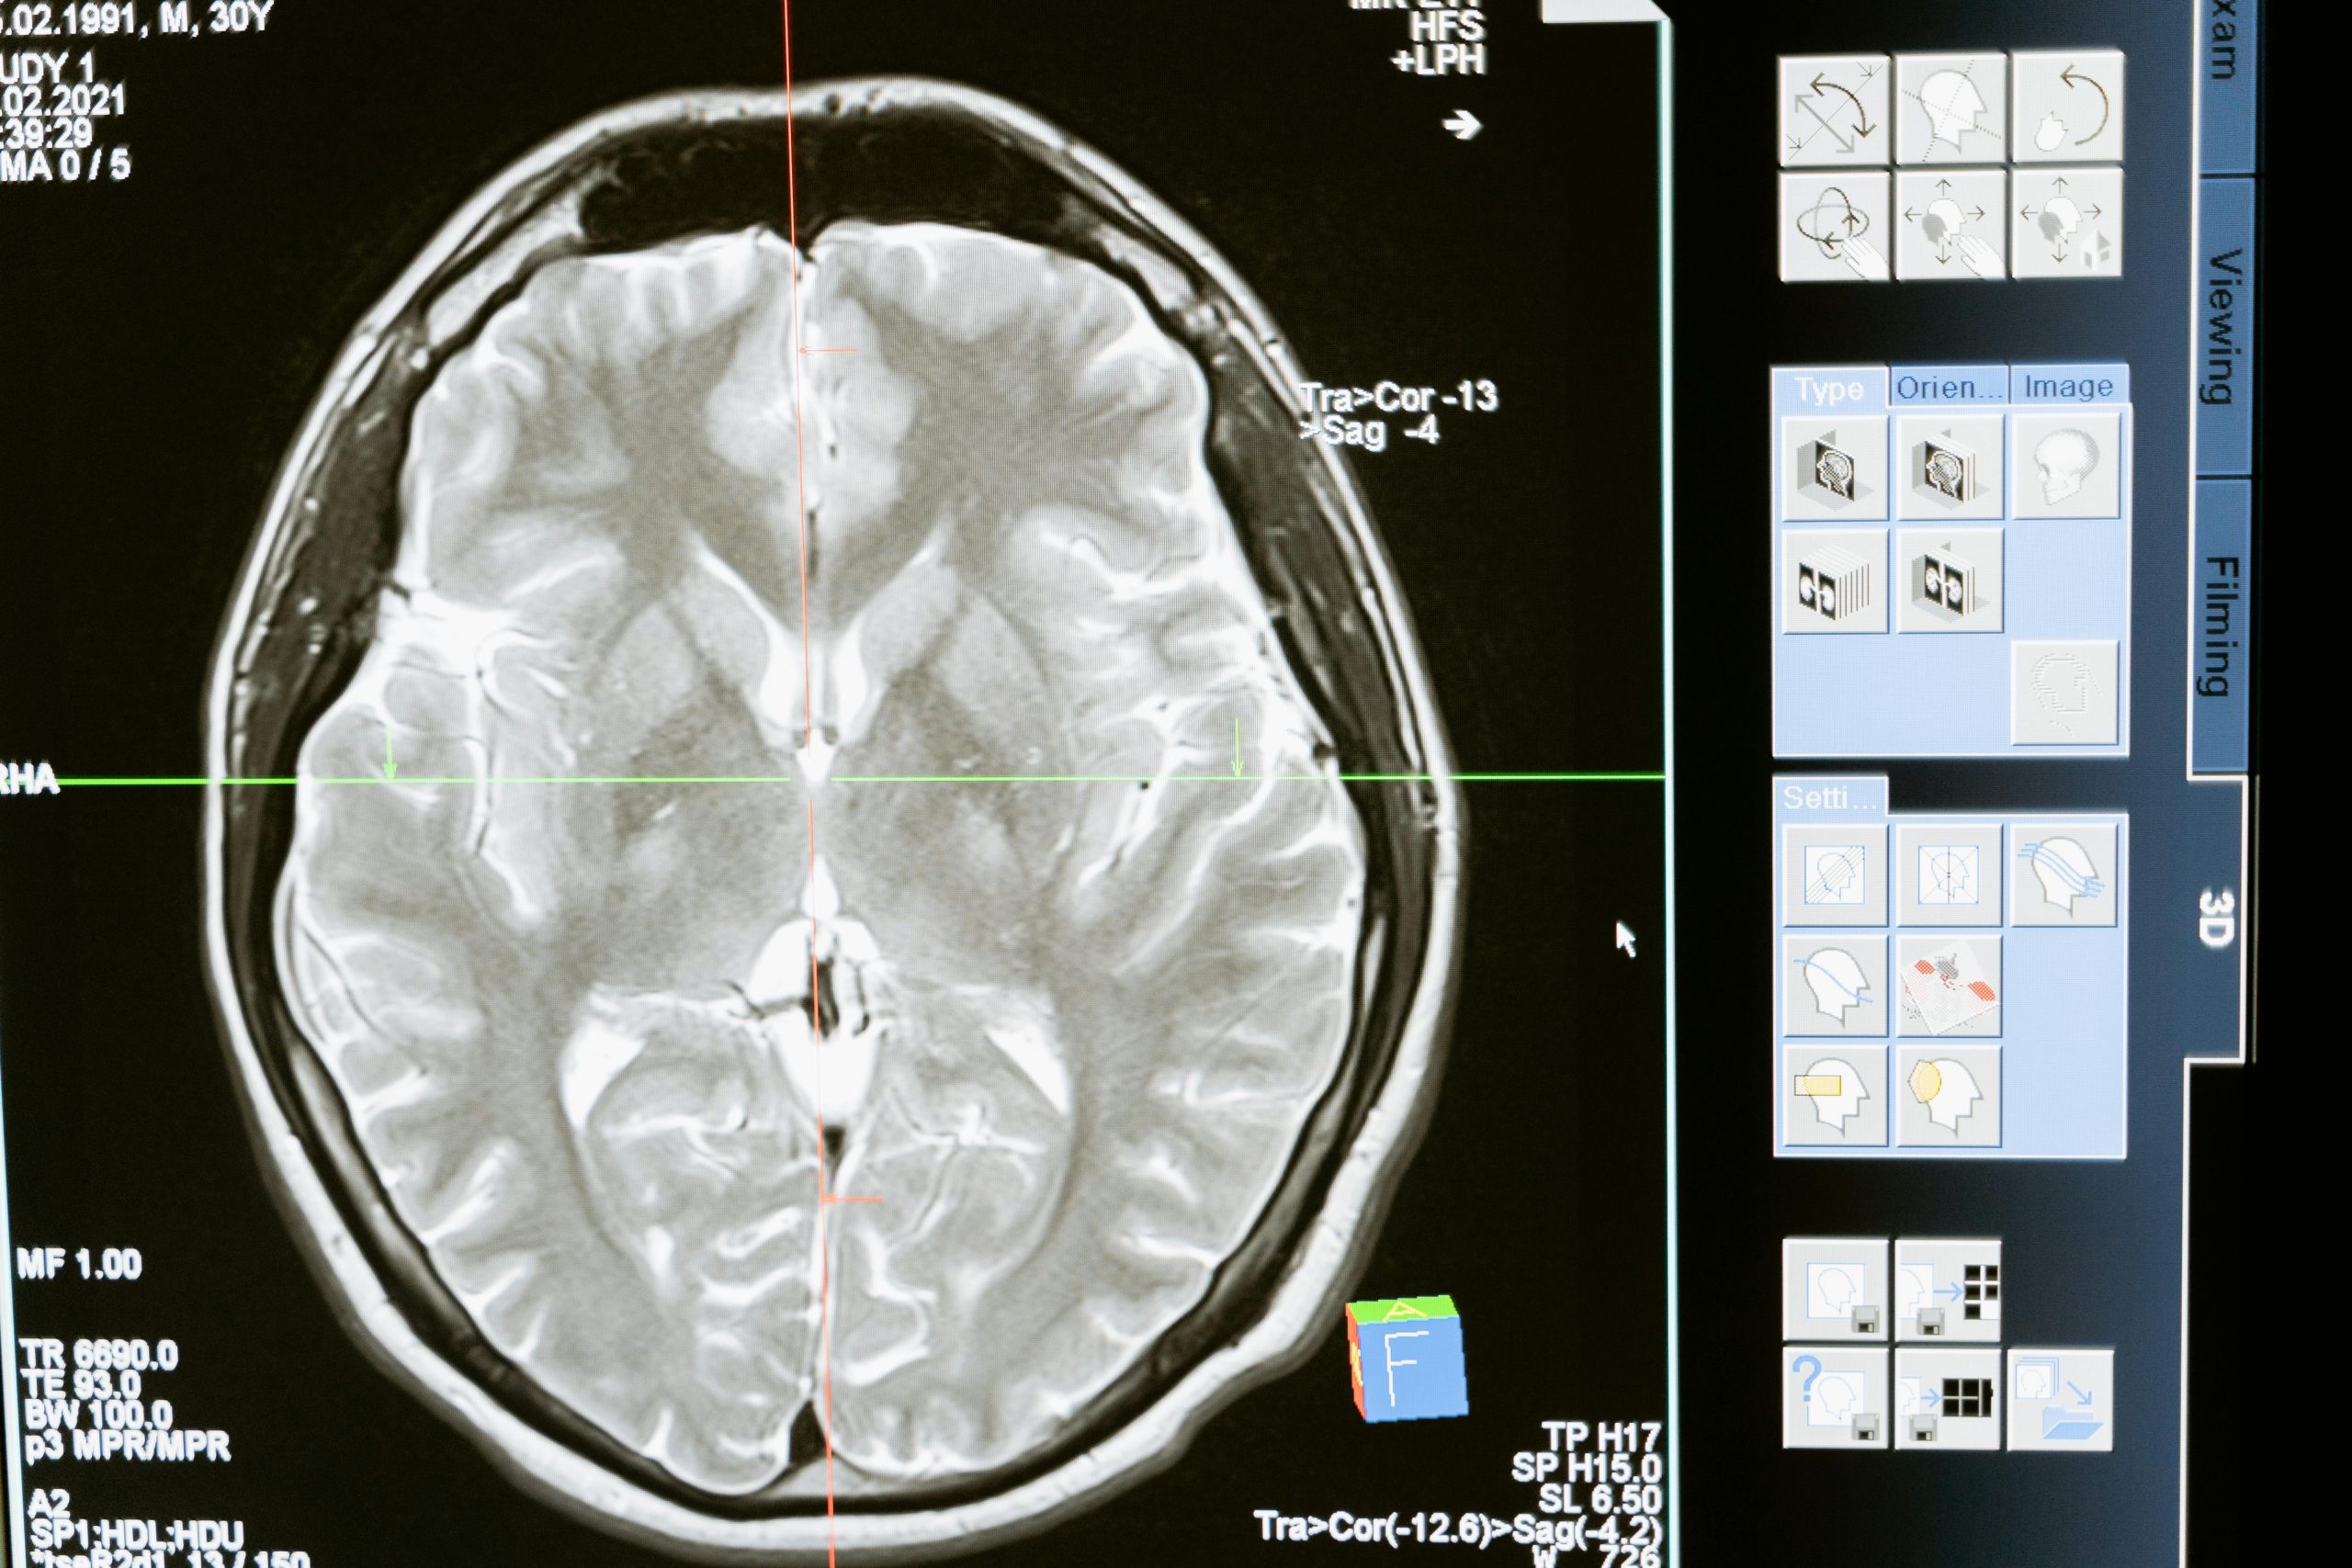

Il cervello è uno degli organi più complessi e importanti del nostro corpo. È responsabile di controllare tutte le funzioni vitali e ci permette di pensare, ricordare, apprendere e agire. Mantenere la salute del cervello è cruciale per garantire un futuro sano e sostenibile. In questo articolo esploreremo l'importanza di prendersi cura del cervello e forniremo consigli pratici per mantenerlo in forma ottimale.